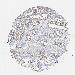

CANCER COLORECTAL CANCER Show tissue menu

Colorectal cancer

Human cancer

Colon adenocarcinoma

Rectum adenocarcinoma